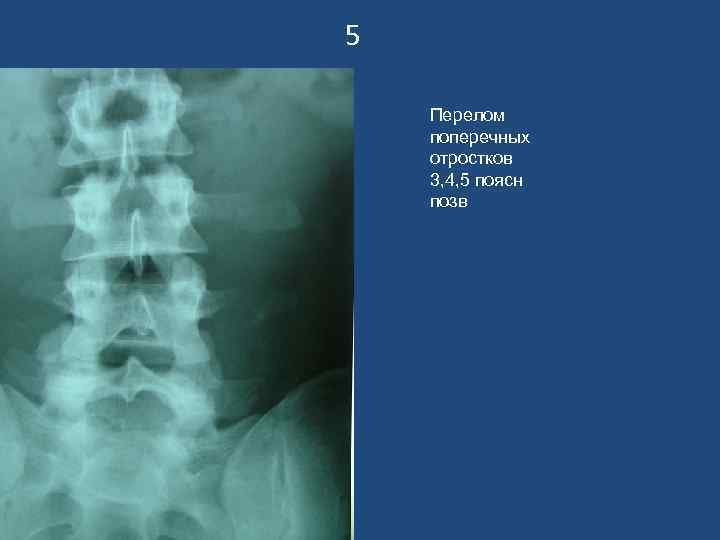

5 Перелом поперечных отростков 3, 4, 5 поясн позв